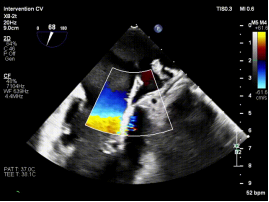

复杂FMR(大GAP):策略性处理实现有效降反流

病例2为复杂功能性二尖瓣反流(FMR),术前影像提示前后瓣叶对合不良,存在明显间隙(GAP),反流程度达极重度。该类病例因瓣叶牵拉明显、张力大,是TEER技术中的典型难点。

针对该病例特点,团队制定个体化诊疗策略,在穿刺位置、器械路径及夹持方式上进行精细设计。术中,团队优化房间隔穿刺高度与位置,匹配GAP结构特点;反复调整导向系统,确保器械垂直对准反流中心;通过多平面及三维TEE确认最佳夹持窗口;采用分步夹持策略,提高瓣叶抓取成功率,确保手术过程平稳。